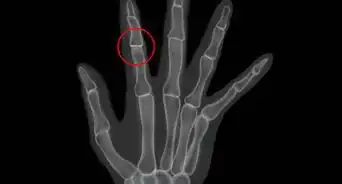

- If you will be undergoing any surgeries under anesthesia and you have RA, your doctor will likely order a neck X-ray to rule out neck and spine changes due to RA. Cervical C1-C2 subluxation is a risk when your neck is propped up during surgery, so your surgeon will need to be aware of any neck problems so they can take precautions.[16]Thanks!